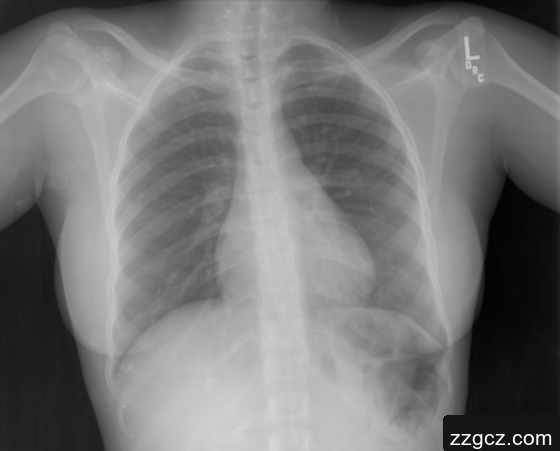

本项目旨在通过深度学习模型自动生成医疗影像的文本描述,特别是针对X光影像的诊断报告编写。该项目基于当前热门的Encoder-Decoder框架,将卷积神经网络(CNN)与循环神经网络(RNN)结合,充分发挥两者在图像特征提取与序列生成方面的优势。在项目中,使用ResNet-101模型从图像中提取特征,再将这些特征输入长短期记忆网络(LSTM),以生成适用于医学诊断的文本描述。医学影像自动报告生成在医疗行业中具有重要应用价值,通过将深度学习模型应用于影像分析,帮助医生减少误诊并节省时间,支持资深医生专注于病人的治疗,尤其适合用于具有重复性工作的影像科。在数据集选择上,本项目使用了印第安纳大学胸部X光图像数据集,专注于FINDINGS部分,项目的文本生成模型将进一步增强医疗图像领域中自动化辅助诊断的能力。

本项目使用的数据集为印第安纳大学胸部X射线集合(IU X射线),该数据集包括7470对胸部X射线图像及其相应的诊断报告。每张图像对应的报告包含多个部分(如印象、发现等),项目仅选择FINDINGS部分用于生成影像描述文本。该数据集图像质量高,内容涉及广泛的医学诊断标签,平均每张图像包含2.2个标签和约5.7个句子,这使得模型能基于丰富的语义特征生成专业的影像描述。